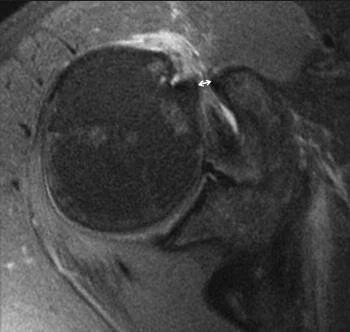

Subcoracoid impingement

- Subcoracoid impingement is defined as impingement of the subscapularis between the coracoid and lesser tuberosity, especially when the arm is in adduction,flexion, and internal rotation

- CT scan obtained with the arms crossed on chest is helpful to make the diagnosis: a coracohumeral distance of < 6 mm is considered abnormal (normal is 8.7 mm in the adducted arm 6.7 mm in the flexed arm)

- MRI is useful to evaluate the rotator cuff condition